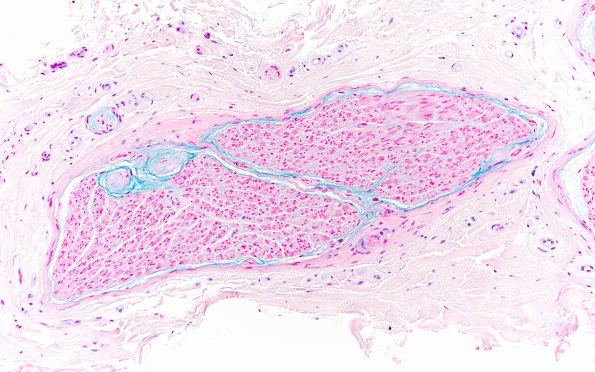

Washington University Experience | PERIPHERAL NEUROPATHY | 1 NORMAL NERVE ANATOMY | 8 Renaut bodies | 2B1 Renaut bodies, (Case 2) Alcian blue 20X 1a

2B1,2 Alcian blue stains the wispy portions of the RB and extends in a subperineurial band more generally. (Alcian Blue)